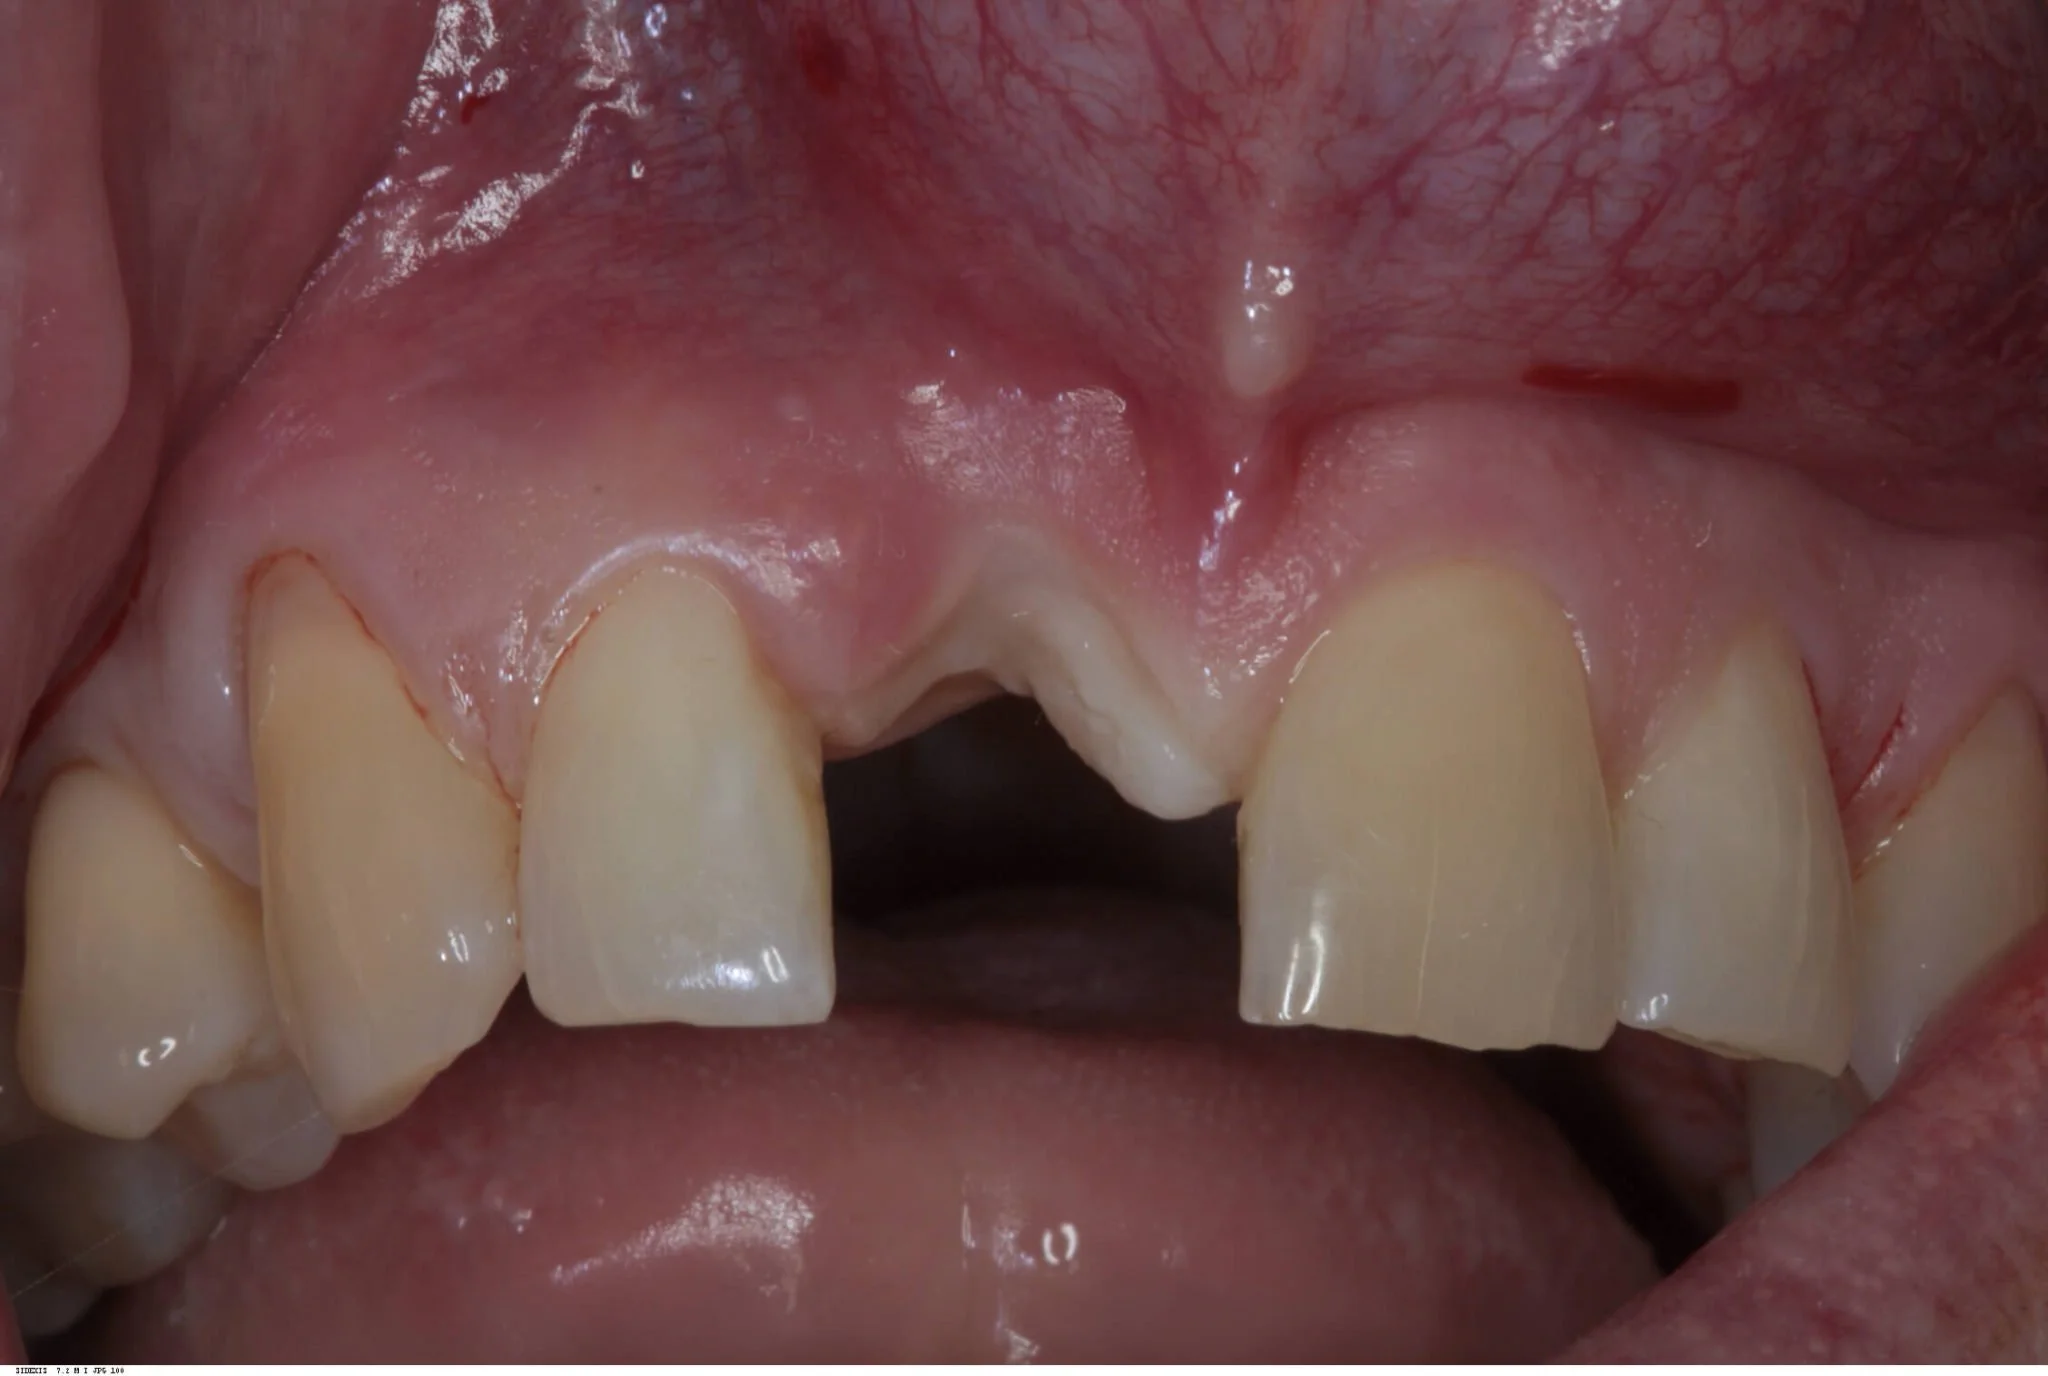

Post Extraction

Due to the patient’s thin biotype, and very little existing labial plate seen on the cone beam radiograph, this treatment was carried out as a delayed two stage procedure. Therefore, the tooth was extracted and a provisional partial denture provided until complete soft tissue healing had occurred eight weeks later. This follows the early placement protocol as described in the ITI study guides.